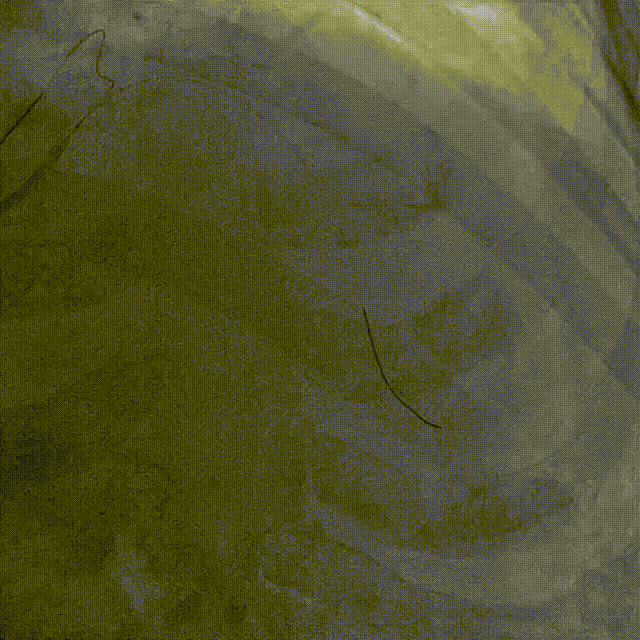

介入经过——最后影像

7,给与4.0x15mm非顺应性球囊进行高压后扩张,压力维持在16~20atm。最后检查血管影像。